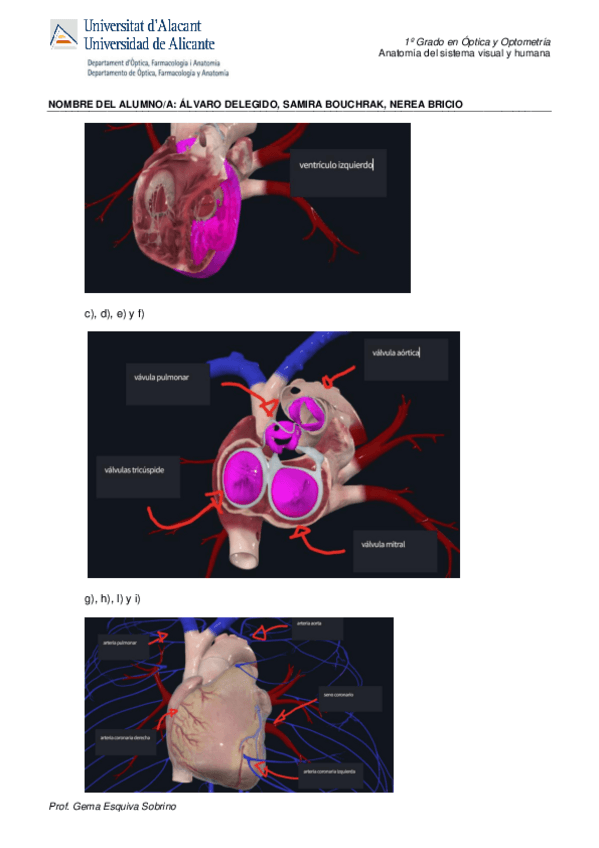

Practica-1-lab-Anatomia.pdf